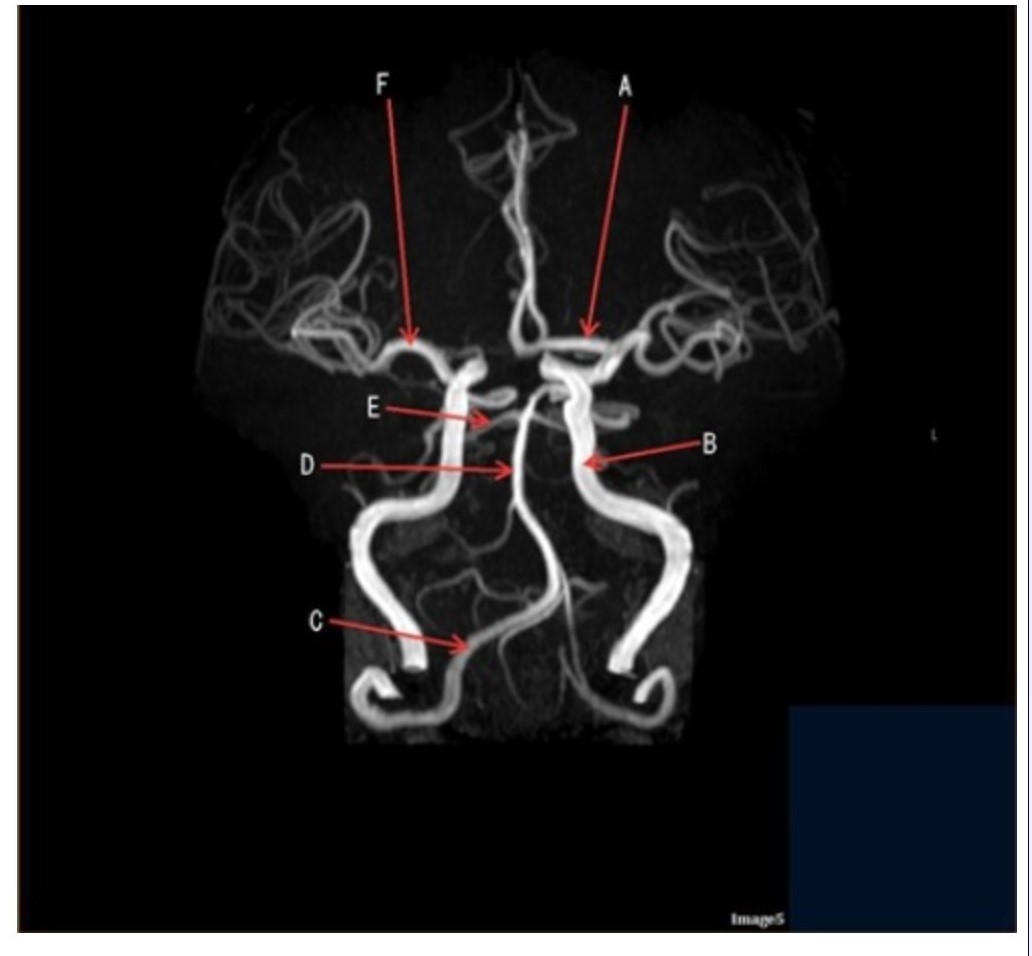

Letter D in Image 5 is pointing to:

A. Anterior cerebral artery

B. Internal carotid artery

C. Basilar artery

D. Posterior cerebral artery

E. Middle cerebral artery

Letter F in Image 5 is pointing to:

A. Anterior cerebral artery

B. Internal carotid artery

C. Basilar artery

D. Posterior cerebral artery

E. Middle cerebral artery

Image 5 is an example of an:

A. MRI brain

B. MRV sagittal sinus

C. MRS single voxel

D. MRA Circle of Willis

Letter B in Image 5 is pointing to:

A. Anterior cerebral artery

B. Internal carotid artery

C. Basilar artery

D. Posterior cerebral artery

E. Middle cerebral artery

Letter C in Image 5 is pointing to:

A. Vertebral artery

B. Internal carotid artery

C. Basilar artery

D. Posterior cerebral artery

E. Middle cerebral artery

Letter E in Image 5 is pointing to:

A. Anterior cerebral artery

B. Internal carotid artery

C. Basilar artery

D. Posterior cerebral artery

E. Middle cerebral artery

Letter A in Image 5 is pointing to:

A. Anterior cerebral artery

B. Internal carotid artery

C. Basilar artery

D. Posterior cerebral artery

E. Middle cerebral artery